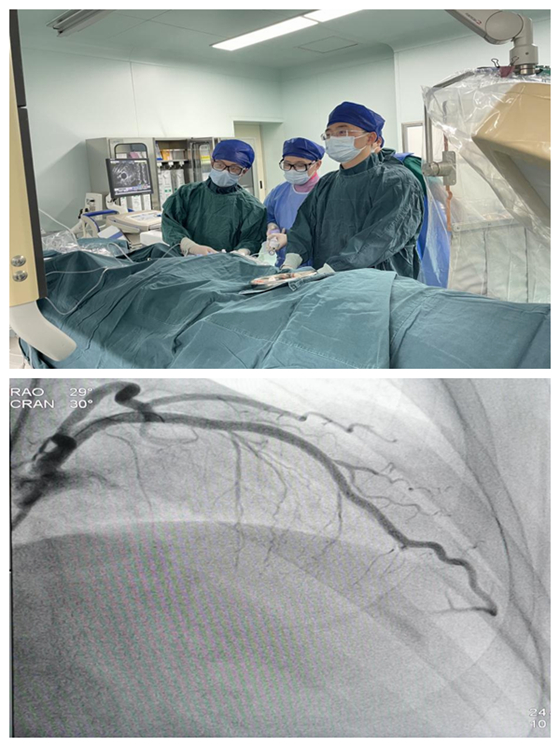

近日,湘雅常德医院胸痛中心接收一位急性广泛前壁心肌梗塞的患者。患者从进入医院大门到导丝通过病变,湘雅常德医院胸痛中心仅用了24分钟,完成支架植入术总共才花费29分钟(远远低于...